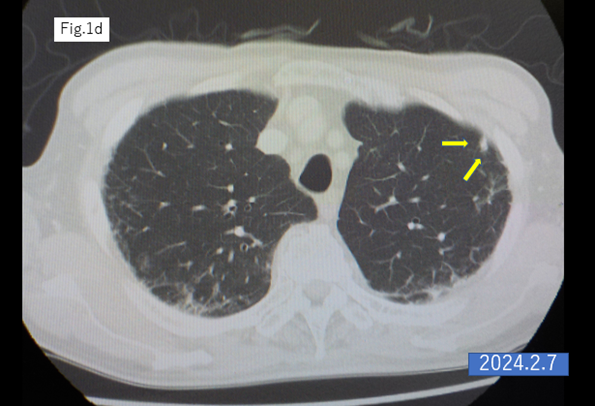

An 87-year-old male underwent laparoscopic left hemicolectomy with a diagnosis of adenocarcinoma of the descending colon in December 2021. Lung metastasis was found in the left upper lobe 6 months postoperatively, and it increased in size after 9 months from the surgery (Figures 1a,b). The patient began S-1 plus oxaliplatin (SOX) treatment with first-line chemotherapy consisting of oral S-1 (a mixed drug of tegafur, gimeracil, and oteracil potassium) at a dose of 50 mg twice daily for 2 weeks following by 1-week off schedule, and intravenous oxaliplatin (100 mg/m2) given on day 1 of a 3-week cycle [2,3], was started in October 2022.The lung metastasis was shrinking within 23 cycles of SOX therapy (Figures 1c–f). The 24th cycle of SOX (only oxaliplatin) was administrated in April 2024, the catheter of venous chemotherapy line of right forearm was removed after finishing the infusion, however bleeding did not stop. The patient had vomiting, chill and pale face, and was transferred to the intensive care unit. The platelet count was rapidly dropped into 2,000/μl from 131,000/μl (pretreatment) within 7 hours and hemoglobin levels decreased from 10.9 g/dl to 8.9 g/dl in the same period, furthermore, dropped into 6.2 g/dl in next 24 hours. Disseminated intravascular coagulation (DIC) score was 8 points, and platelet-associated IgG (PA-IgG) was significantly high (204.0 ng/107 cells; normal < 30>.

Figure 1: CT scan of the lung